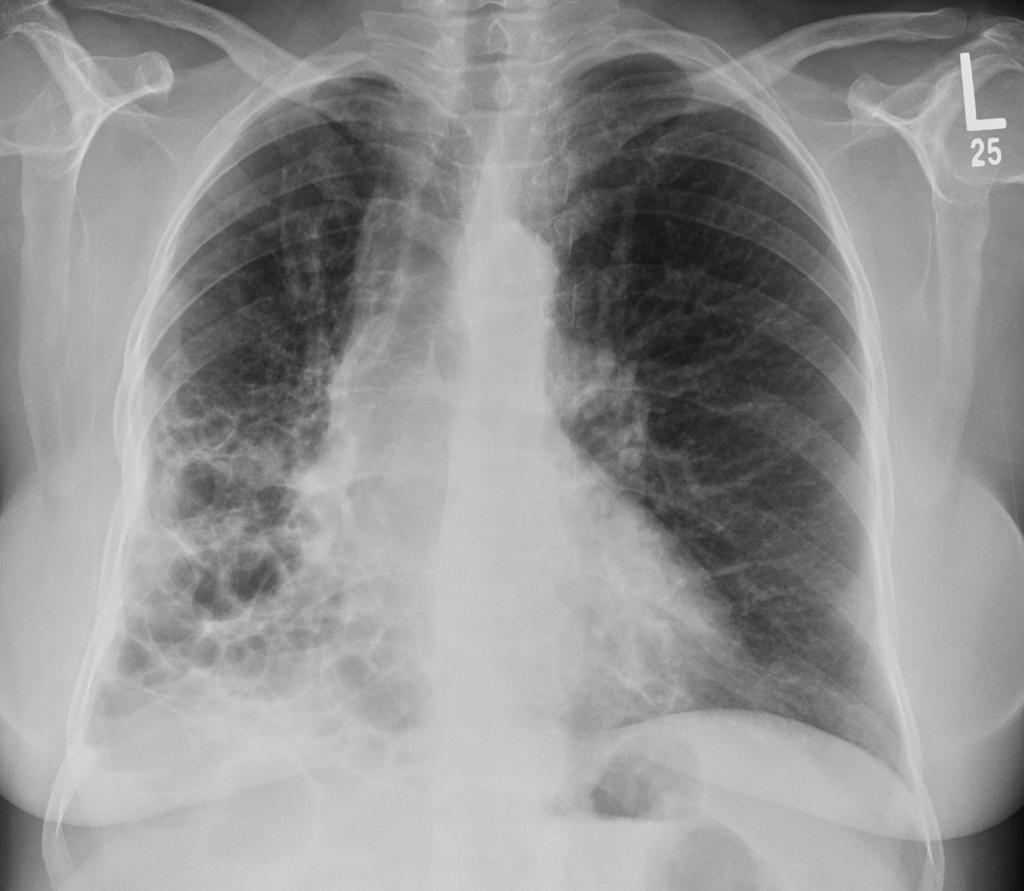

间质性肺疾病的临床表现与症状

你有没有这样的经历:明明以前爬三层楼都不带喘的,现在走几步路就气喘吁吁?或者总是莫名其妙地干咳,吃了止咳药也不管用? 如果这些症状持续出现,你可能需要警惕一种...